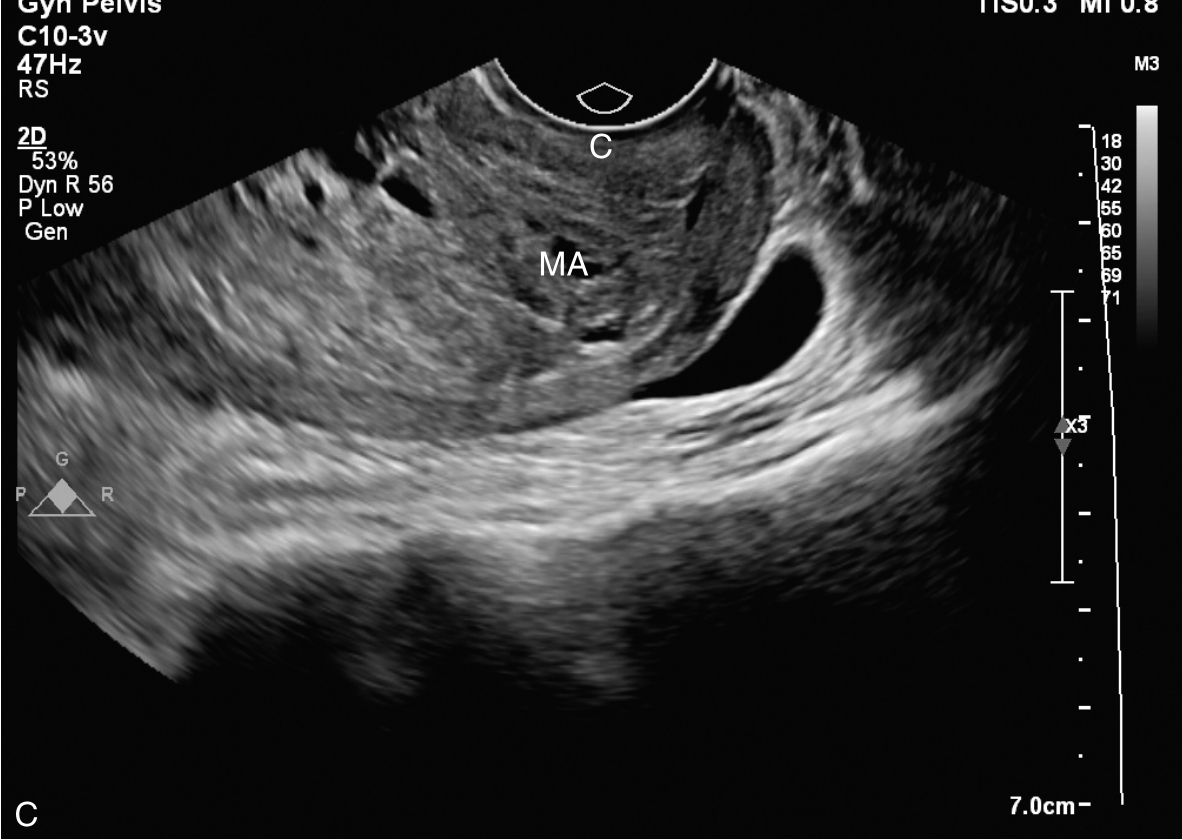

经阴道超声检查见图3-10-1。子宫前位,宫体大小5.6cm×6.9cm×6.5cm,宫腔内查见7.1cm×2.6cm×3.5cm不均质稍强回声,其内回声极不均匀,其内可见多个无回声区,最大无回声区的最大径为0.8cm,周边及其内探及丰富血流信号,该团块与子宫前壁关系密切。宫颈后唇查见囊性占位,大小为2.5cm×1.3cm×1.9cm,囊液清亮,未探及明显血流信号。双附件区未见确切占位。超声检查结果:宫腔内占位,宫颈后唇囊性占位。

图3-10-1 常规超声声像图

A.子宫矢状切面显示宫腔内稍强回声;B.子宫横断面显示宫腔内强回声;C.子宫矢状切面显示宫颈管内占位;D.宫颈管内占位的血流情况;E.宫腔占位的血流情况;F.宫颈囊性占位(箭头所示)。UT:子宫;C:宫颈;MA:肿物。